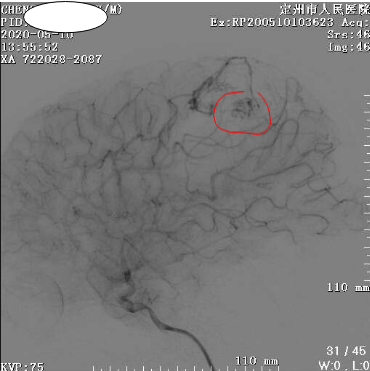

开始,肖主任通过影像发现小雷左顶部动静脉畸形团约3

cm

×1.5cm大小,可见左侧大脑前动脉末端供血,及两根粗大引流静脉引流至上矢状窦。

出血位置顺利找到。

肖主任反复查看脑血管造影,并结合小雷整体情况,与科内医生讨论决定为小雷先介入栓塞动静脉畸形团,根据经验这种情况下只有10

%

-20%的机会能经过介入完全栓塞,如果剩下还有,那就要开颅清除颅内血肿。